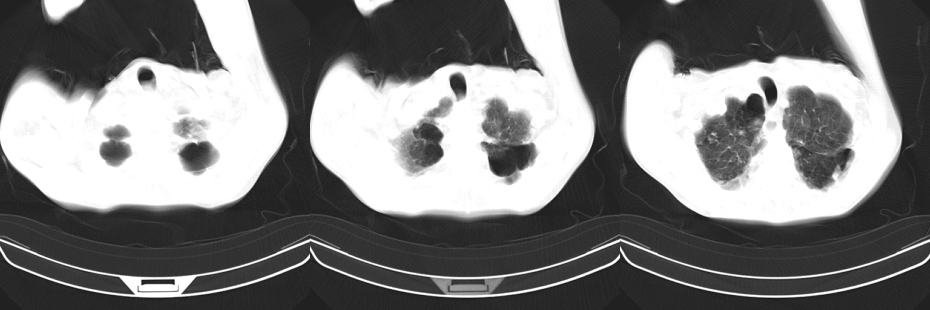

以下是引用mzh123在2007-8-26 19:58:00的发言:[br]两肺弥漫性斑片改变,其中可见大小不等之不规则空洞,结合既往病史还是考虑结核复发及感染。

以下是引用云翔在2007-8-26 20:54:00的发言:[br]这是44岁的肺吗?是否有先天病的基础?干酪性肺炎?